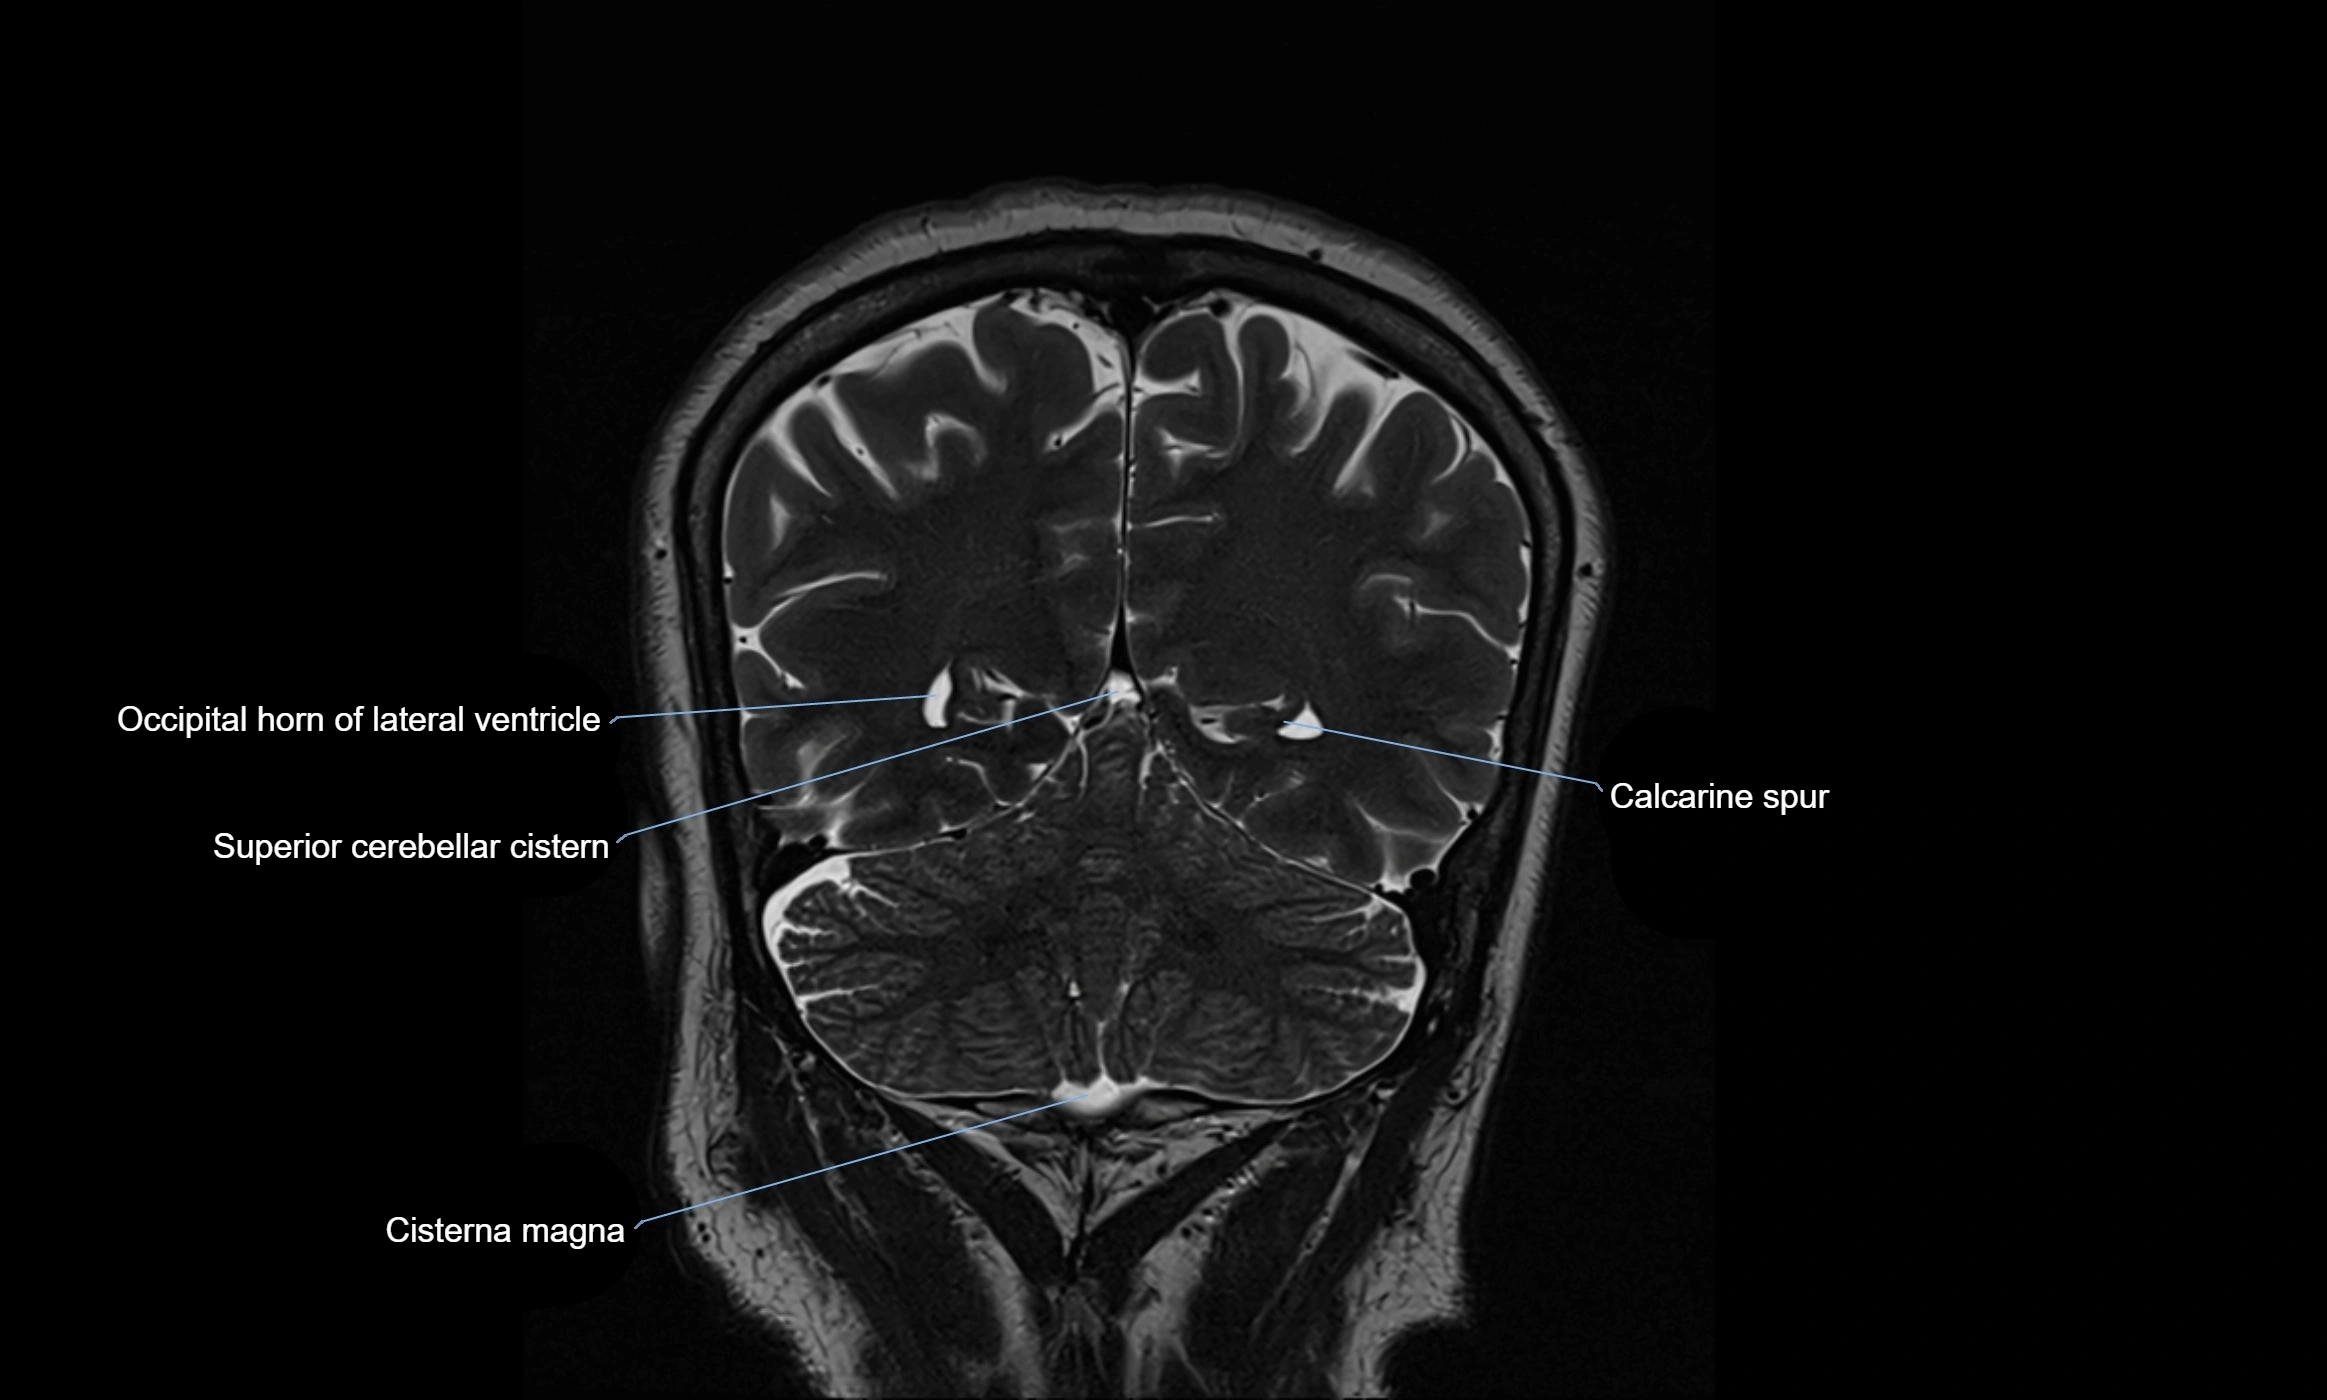

MRI images

image